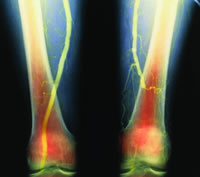

股血管损伤是最常见的血管损伤之一,目前尚无研究确定其生存和并发症发生的相关危险因素。美国一项研究表明,尽管股血管损伤的生存率和保肢率较高,但仍存在较高并发症发生率。发生死亡的独立危险因素包括损伤程度评分>25、在手术室发生凝血紊乱、存在2个或2个以上的血管体征以及年龄>45岁。[J Am Coll Surg 2006,203(4): 512]

该研究纳入298例血管疾病患者中的204例患者,其中动脉损伤204例次,静脉损伤94例次。平均年龄为(29±13)岁,平均损伤程度评分为(17±8)。176例(86%)患者为穿透性损伤,28例(14%)为钝性损伤。对各相关因素进行单变量和多变量分析。

结果表明,总生存率为91%,调整生存率为95%(不包括急诊开胸死亡)。47例(23%)患者发生1个或1个以上的并发症,包括31例(15%)伤口感染、6例(3%)静脉血栓形成、5例(2.5%)出血、4例(2.5%)急性呼吸窘迫综合征(ARDS)和1例(0.5%)动脉血栓形成。死亡预测因素包括年龄>45岁、损伤程度评分>25、股动脉损伤伴随静脉和腹部损伤、低血压、低体温和酸中毒、在手术室发生凝血紊乱等。术后并发症危险因素包括术中低血压、动脉内膜损伤、骨折和胸部损伤。, 百拇医药